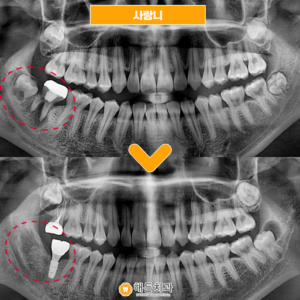

천안아산치과 사랑니발치를 미루게 된다면

천안아산치과 사랑니발치를 미루게 된다면 안녕하세요 🙂 사랑니는 보통 만 17세에서 25세 사이에 맹출 하며, 사람에 따라서 하나도 나지 않거나 4개 모두 자라는 경우도 있습니다. 그런데 이쁜 이름과는 달리 구강…